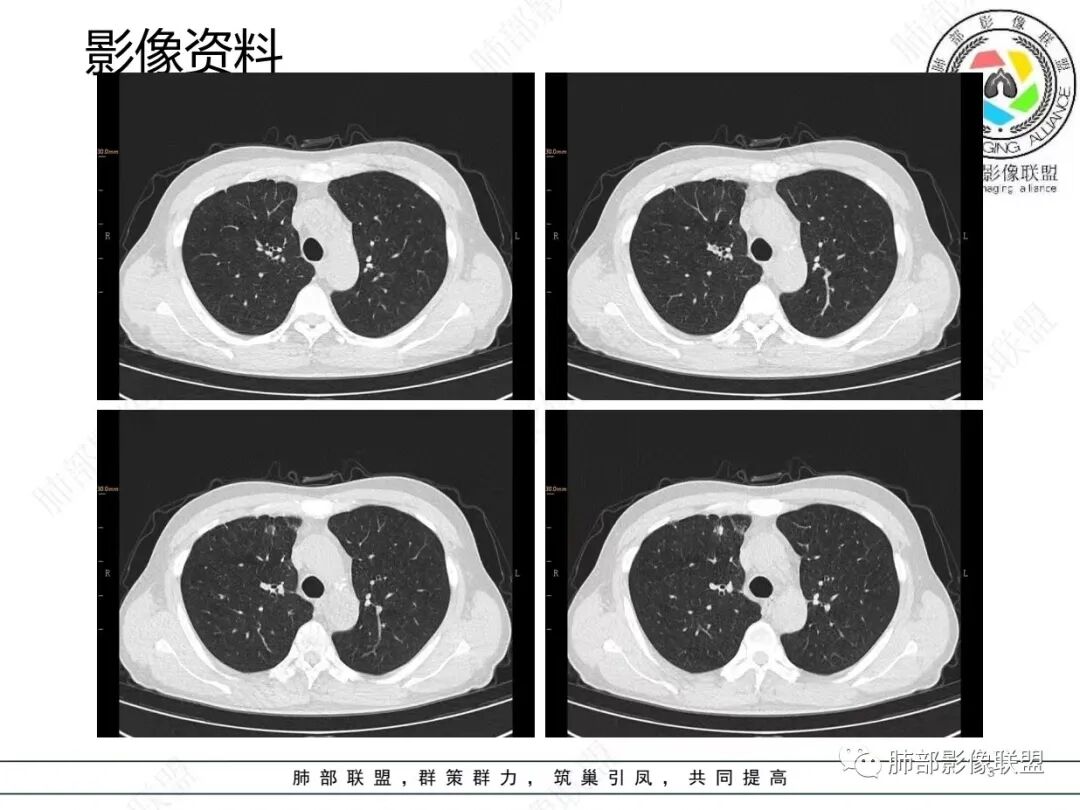

1.临床特点:52岁男性,体检发现肺结节。有吸烟史。非小细胞肺癌相关抗原与神经元烯醇化酶轻度升高。2.影像特点:右肺上叶前段可见不规则结节影,整体膨隆,可见浅分叶,周围局部可见边界清楚的磨玻璃影。可见血管集束征及脐凹征,临近叶间胸膜受牵拉凹陷,局部支气管到达病灶边缘后显示截断。3.病例小结:中老年吸烟男性,右肺上叶前段不规则结节,膨胀感较明显,收缩力强,支气管截断,加上边界清楚的磨玻璃影。符合浸润性腺癌表现。

4.相关知识:浸润性肺腺癌分为:附壁状、腺泡状、乳头状、微乳头状、实体型,较少见的生长模式包括浸润性黏液型、胶样、肠型和胎儿型。腺癌影像表现为磨玻璃影、部分实性结节、实性结节或实变。

普通型肺腺癌有哪些CT特点?

1.周围型:指从组织学上分析,起源于周围肺泡上皮及末梢细支气管上皮

2.有附壁生长的成分(GGO)。

5.具有收缩力表现:胸膜牵拉凹陷、兔耳征、毛刺征、纠集征等。

6.支气管充气征与支气管牵张扭曲。

7.分叶征。

8.膨胀边缘与胸膜处锐角。